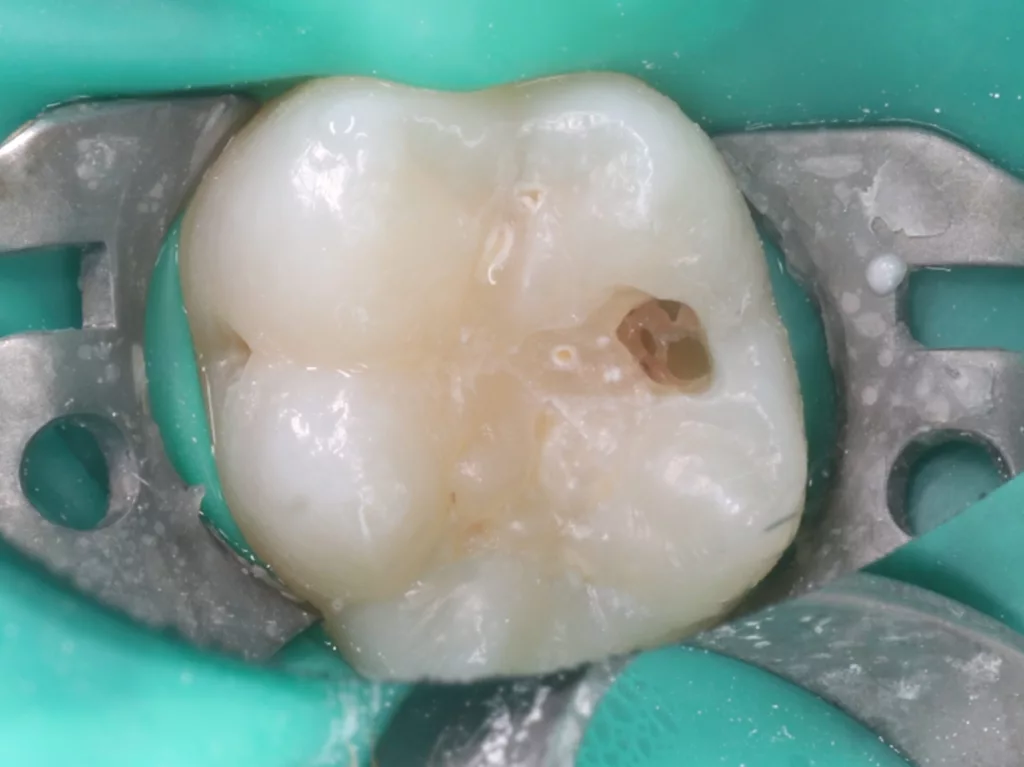

Unter Lokalanästhesie mit dem STA-System (Milestone Scientific, USA) und Septanest 1/200 000 (Septodont, Frankreich) wurde die überstehende Gingiva mit dem Khors Koagulator (Эctatex, Ukraine) koaguliert und der Bereich unter Kofferdam kontaminationsfrei dargestellt (Klammer U67, KSK Dentech, Japan). Die schmalen Fissuren wurden mit dem Fissurenbohrer CD-53F (Mani, Japan) erweitert, um anschließend mittels RONDOflex plus 360 (KaVo Dental, Deutschland) und Pulver 27 µm vollständig gereinigt werden zu können. Es konnte weder durch visuelle Inspektion noch Sondierung mit 0.08 H-file (Mani, Japan) ein Defekt des Zahnschmelzes festgestellt werden. Unter Berücksichtigung der Integrität des Zahnschmelzes, der Symptomlosigkeit, des Behandlungszeitpunktes, Alters des Kindes und Wachstums der Zahnwurzeln fiel gemeinsam mit den Eltern die Wahl auf eine konservative Therapie. Es wurde eine Fissurenversiegelung mit Clinpro Sealant (3M, USA) unter Anwendung eines adhäsiven Behandlungsprotokolls mit Optibond FL (Kerr, USA) durchgeführt. Dieser klinische Fall ist dahingehend einzigartig, da alle anderen ersten und zweiten Molaren des Kindes ebenso von einer PEIR betroffen waren (Grad 1 bis 2 der Läsion nach Seow) (Abb. 3 und 12). Normallerweise ist nur ein Zahn bei einer Patientin oder einem Patienten betroffen. Die Zahnkronen der anderen betroffenen Zähne erwiesen sich bei der klinischen Untersuchung als intakt; die radioluzenten Läsionen innerhalb des koronalen Dentingewebes waren wesentlich kleiner als die von Zahn 36. Daher wurde auch bei diesen Molaren das gleiche Behandlungsprotokoll angewendet und nur eine Fissurenversiegelung durchgeführt.

Im Rahmen der jährlichen Kontrolluntersuchung wurde bei einem achtjährigen Mädchen auf der routinemäßig angefertigten Röntgenaufnahme eine mittelgroße PEIR des Zahnes 46 (Grad 2 der Läsion nach Seow) entdeckt (Abb. 43). Die Patientin war komplett beschwerdefrei und der Zahnschmelz des betroffenen Zahnes sah intakt aus (Abb. 44 und 45). Weil auch hier der PEIR-Defekt gräulich durchschimmerte (Abb. 44 und 45) und der Zahn bereits seit einem Jahr durchgebrochen war, entschieden wir uns in diesem Fall, den Defekt klassisch mit Komposit zu restaurieren. Unter Lokalanästhesie mit Septanest 1/100 000 (Septodont, Frankreich) wurde zunächst Kofferdam mithilfe der Klammer U67 (KSK Dentech, Japan) gelegt (Abb. 45). Weder visuell noch mittels Sondierung konnte eine Verbindung zur Läsion festgestellt werden. Deswegen wurde an der Stelle, an welcher der PEIR-Defekt gräulich schimmerte, intakter Zahnschmelz der lingualen Querfissur entfernt (Abb. 46). Innerhalb der Läsion wurde nekrotisches intrakoronales Weichgewebe vorgefunden (Abb. 47), das problemlos mittels RONDOflex plus 360 (KaVo Dental, Deutschland) mit dem 27-µm-Pulver vollständig entfernt werden konnte. Der Boden des Defektes zeigte eine glatte, runde Form sowie helles, hartes und intaktes Dentin. Eine Präparation war nicht erforderlich, es wurde lediglich die Zahnschmelzkante geglättet (Abb. 48). Für die Restauration kamen erneut das Adhäsiv Optibond FL (Kerr, USA) und das Komposit Estelite ASTERIA OCE, A2B und Universal Flow AO2 (Tokuyama, Japan) zur Anwendung (Abb. 49). 6 Monate nach der Behandlung zeigte sich das Ergebnis sowohl aus klinischer als auch radiologischer Sicht stabil wie die Abbildungen 50 und 51 zeigen.